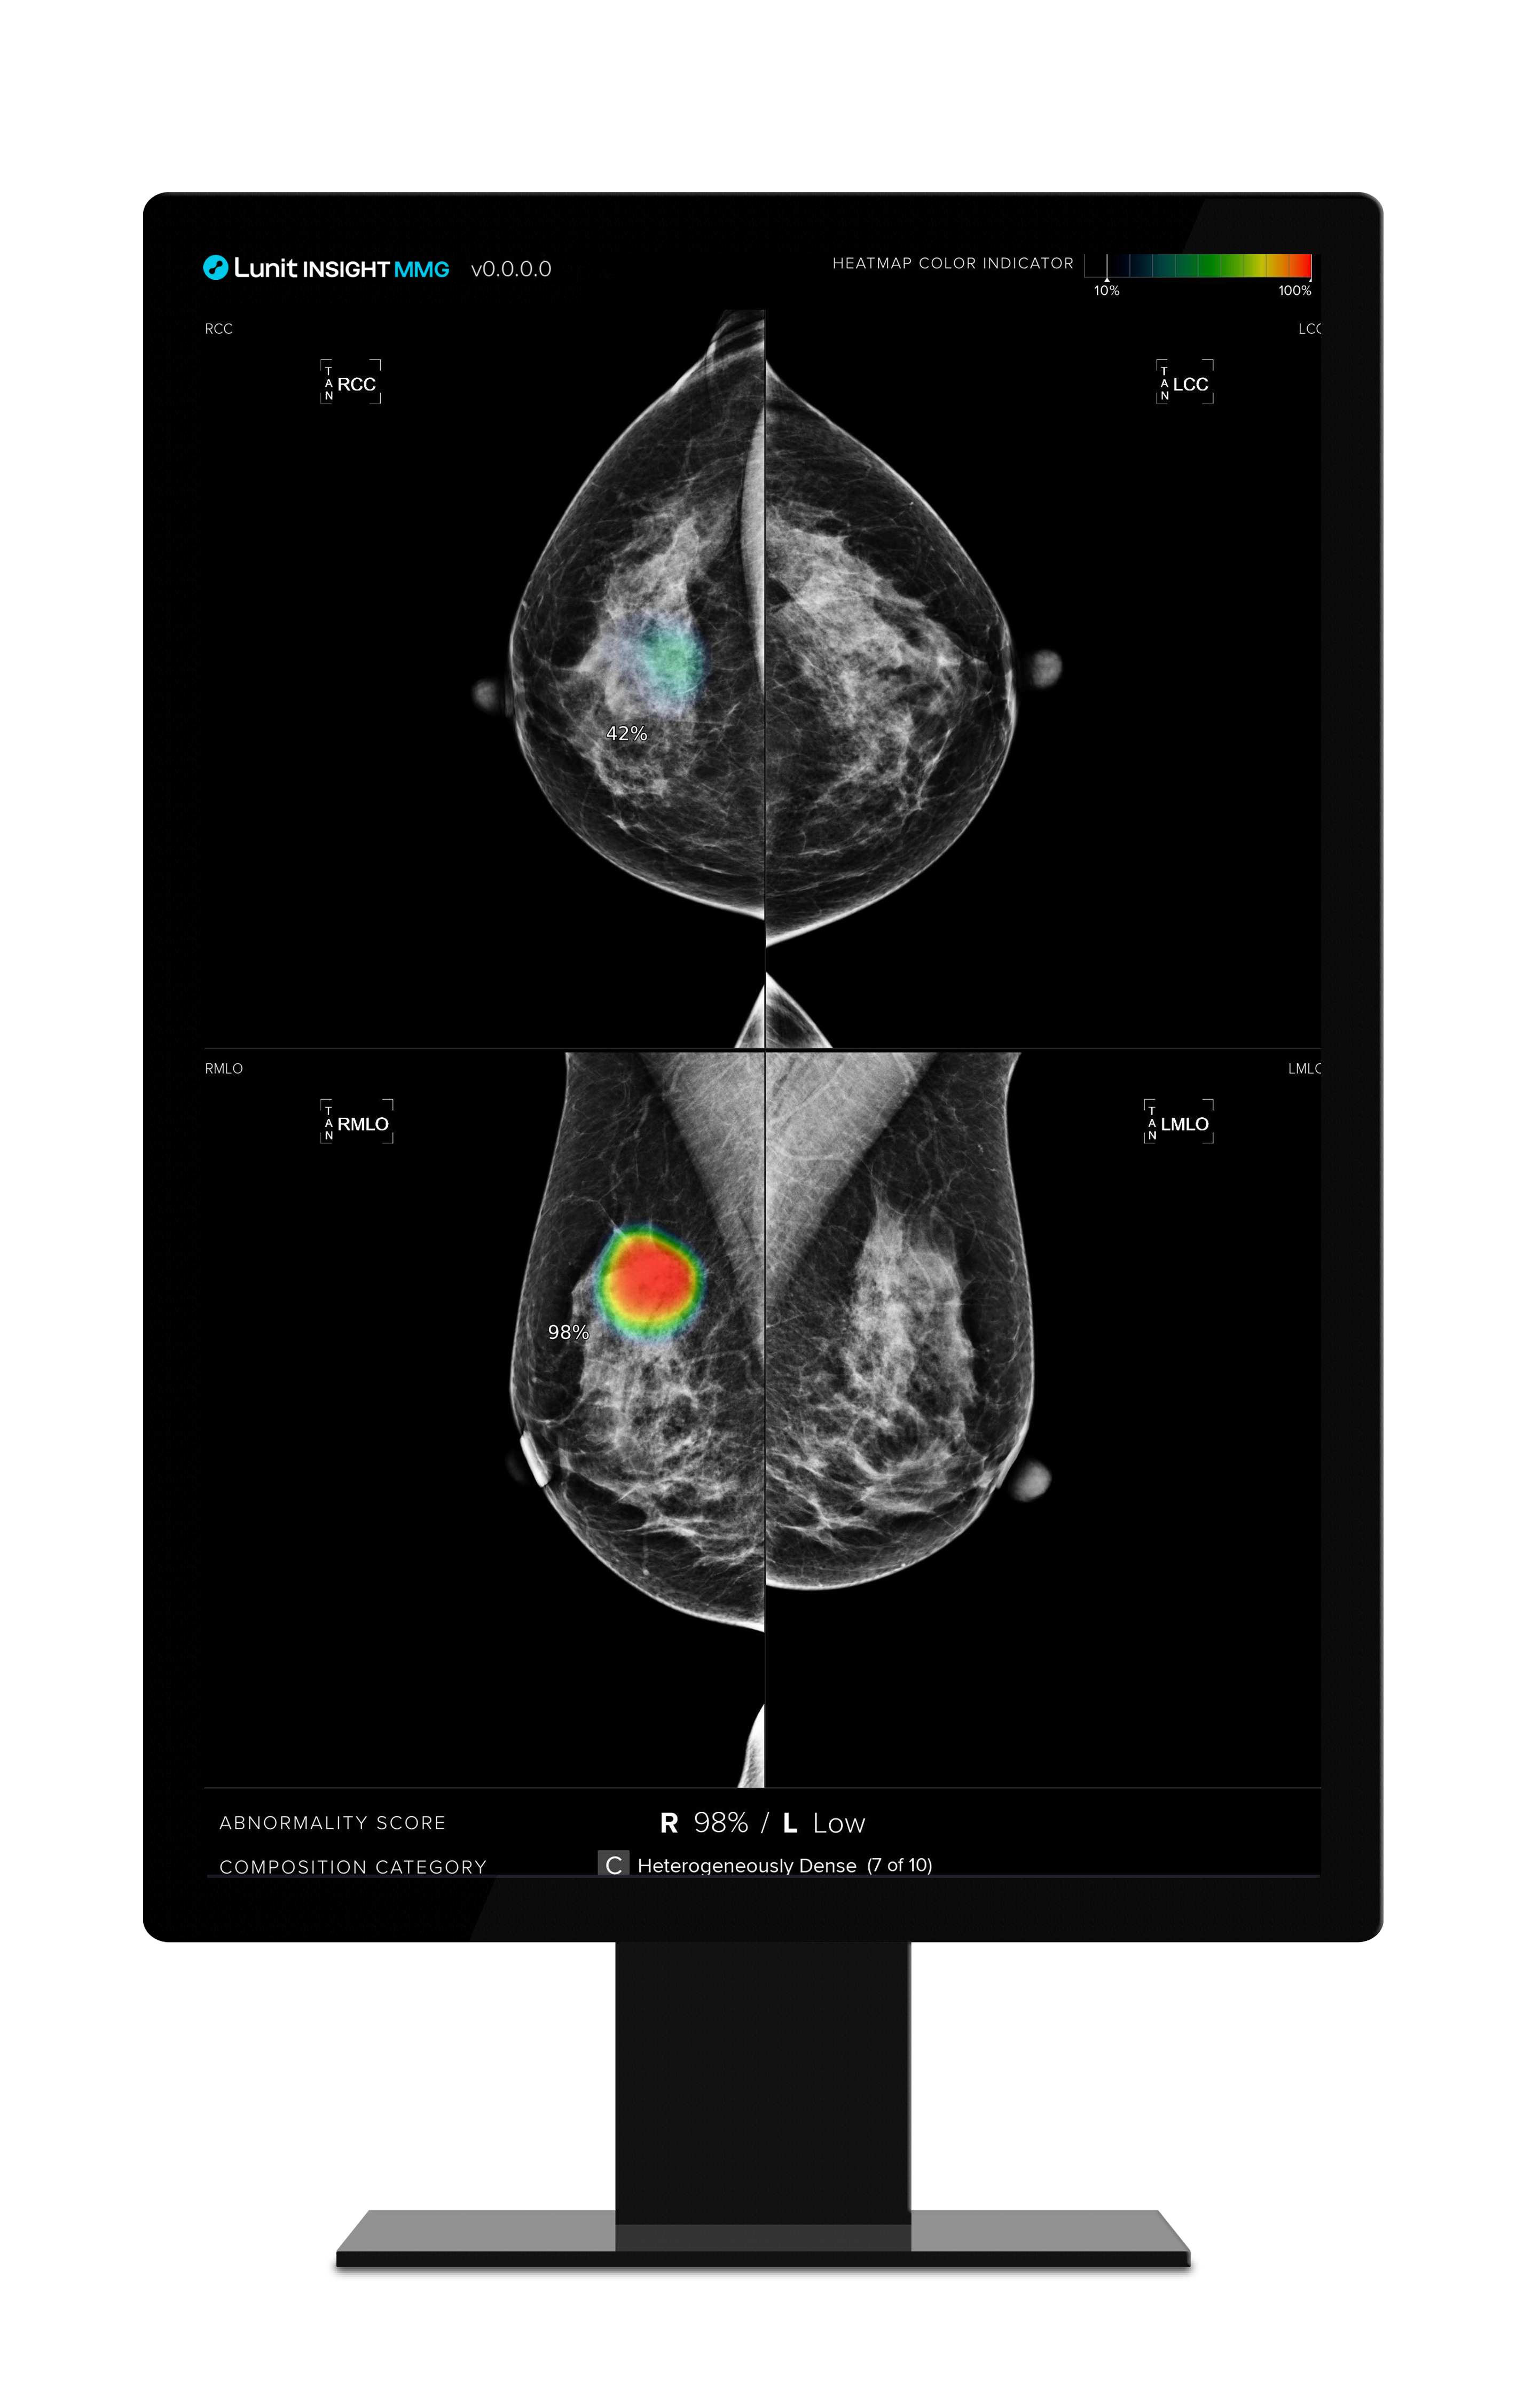

루닛은 전체 3단계의 프로젝트 과정 중 1단계에서 약 65만 건의 유방촬영 영상을 AI 영상분석 솔루션 ‘루닛 인사이트 MMG’로 분석, 기술의 정확성과 신뢰성을 입증했다.

이번 2단계에서는 검진 데이터 약 20만 건을 활용해 내년 6월까지 약 6개월 간 추가 검증이 진행된다. 2단계는 실제 설치에 앞서 루닛 솔루션의 최적화 및 유효성 검증 작업(Prospective Validation)을 진행하며, 이 과정에서 최근 미국 식품의약국(FDA)의 승인을 받은 3차원 유방단층촬영술 AI 영상분석 솔루션 ‘루닛 인사이트 DBT’에 대한 평가 작업도 진행될 예정이다.

이후 마지막 3단계에서는 BSNSW 의료진이 루닛 인사이트 MMG를 활용해 검진을 수행할 예정이다.